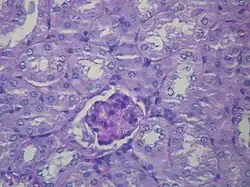

| Microscopic image of diabetic glomerulosclerosis, the main cause of nephrotic syndrome in adults. | |